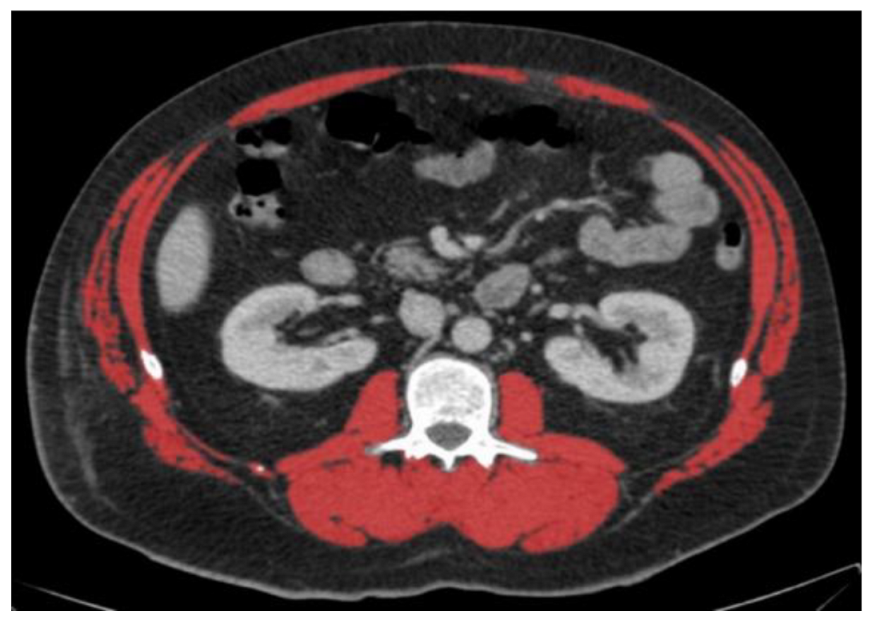

3.2. Diagnosis of Low Muscle Mass in Two Selected Patients

![]() | ![]() | All male patients (n = 118) * | |

| Sex | Male | Male | Male |

| Age (years) | 51 | 31 | 63.6 (51.4–71.3) |

| Height (cm) | 160 | 197 | 177.1 ± 7.3 |

| Weight (kg) | 93 | 85 | 79.1 ± 14.0 |

| BMI (kg/m2) | 36.3 | 21.9 | 25.2 ± 4.4 |

| CT area (cm2) | 939.8 | 592.4 | 749.8 ± 187.6 |

| A: Diagnosis of low or normal muscle mass according to sex-specific cut-offs set at the mean of our study population | |||

| SMA (cm2) | 150.6 (normal) | 162.9 (normal) | 148.3 ± 23.7 |

| SMA/height2 (cm2/m2) | 58.8 (normal) | 42.0 (low) | 47.3 ± 7.6 |

| SMA/BMI (cm2/(kg/m2)) | 4.1 (low) | 7.4 (normal) | 6.0 ± 1.0 |

| B: Diagnosis of low or normal muscle mass according to published cut-offs for low muscle mass | |||

| Derstine, 2018: SMA by sex [8] | Normal | Normal | |

| Derstine, 2018: SMA/height2 by sex [8] | Normal | Low | |

| Mourtzakis, 2008: SMA/height2 by sex [13] | Normal | Low | |

| Prado, 2008: SMA/height2 by sex [17] | Normal | Low | |

| Martin, 2013: SMA/height2 by sex and BMI [3] | Normal | Low | |

| Martin, 2018: SMA/height2 by sex and age [16] | Normal | Low | |

| van der Werf, 2018: SMA by sex, age and BMI [10] | Low | Normal | |

| van der Werf, 2018: SMA/height2 by sex, age and BMI [10] | Normal | Normal | |

| Tanaka, 2020: SMA/BMI by sex [9] | Low | Normal | |